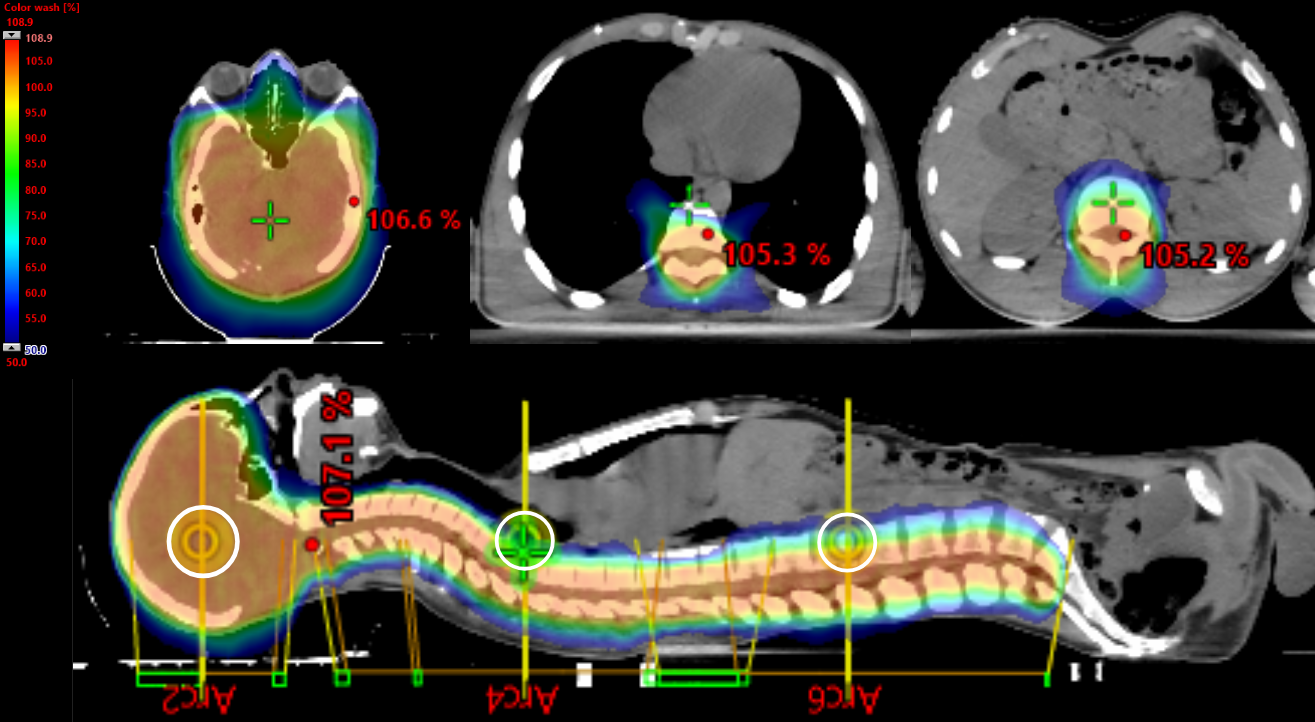

Regarding the RT plan, Table 1 and Table 2 report all dosimetric data, while Figure 2 presents the dose distributions in the sagittal and transversal views.

Figure 2. Sagittal views and transversal views. Color wash range: 50% to 107%. The white circle represents the three isocenters of the CSI plan.